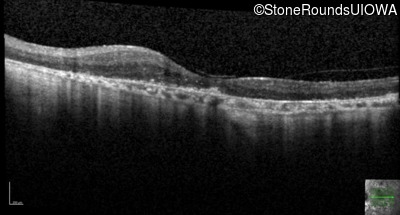

Age at visit: 62 years (Visit 2)